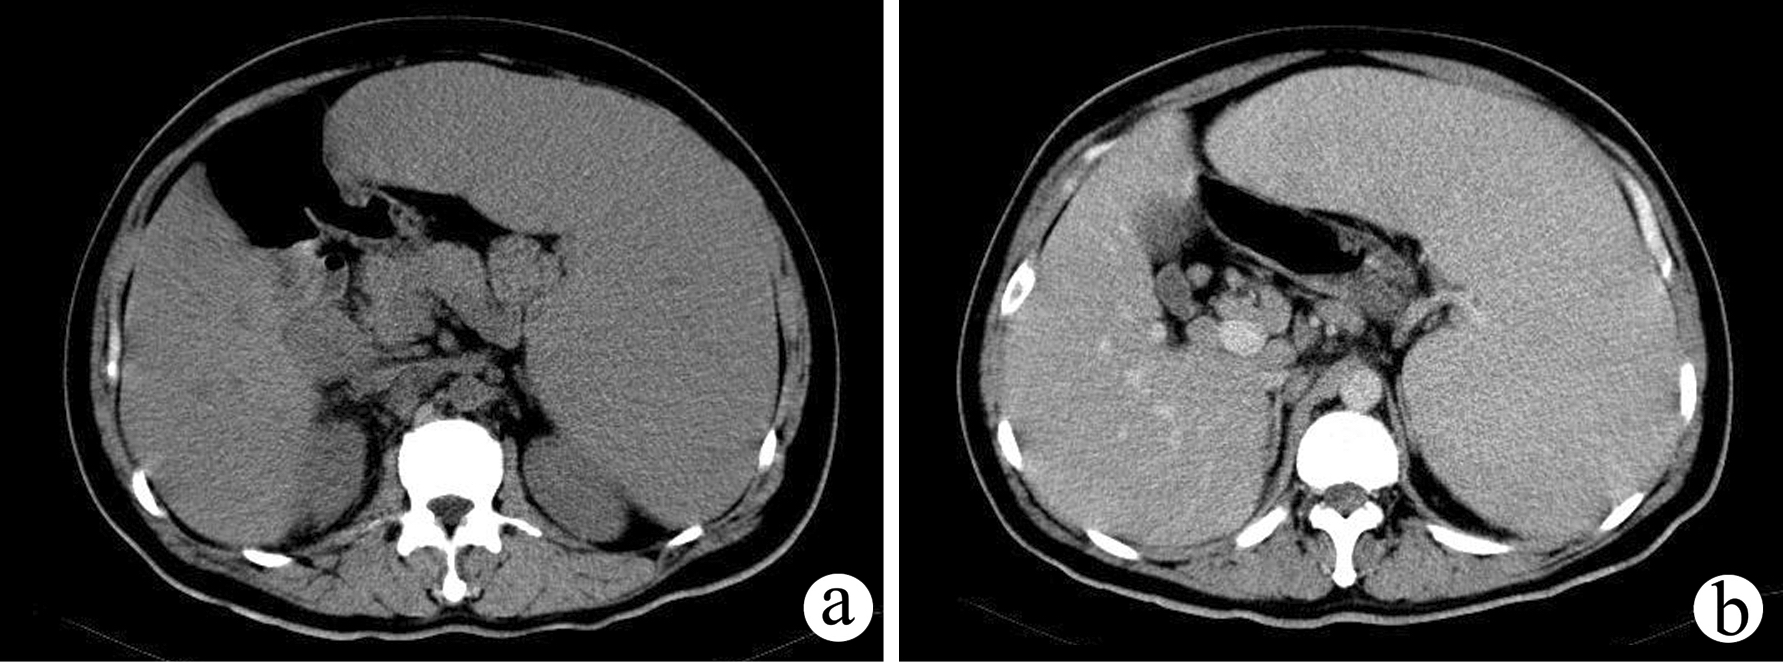

脾大是肝不好?肝硬化与脾肿大有相关性,有哪些症状?做什么检查[s0]高度脾肿大图[s1]轻度脂肪肝引起的脾肿大需要治疗吗[s2]脾大的原因和危害是什么又该如何治疗呢[s3]一.什么是脾脏肿大? 当出现脾大时,一定要高度警惕!下面就一起来看下吧。[s4]出现脾脏肿大就一定是肝硬化了吗?[s5]脾肿大 全网资源[s6]脾肿大一定要切除脾脏吗?[s7]小症状大学问:大牛直播讲解「肝脾肿大」的鉴别诊断与治疗[s8]术后病理结果:淤血性脾肿大伴出血性梗死.[s9]查看:脾脏肿大还能恢复正常吗?[s10]脾脏肿大,发紫图片为检测到感染14天后的猪.[s11]图片[s12]脾大的原因和危害,如何治疗[s13](正常脾脏与肿大脾脏对比)影像学检查:若触诊脾肿大,则需要进一步做[s14]脾肿大 全网资源[s15]白血病有脾脏肿大怎么缩小?[s16]脾肿大[s17]脾肿大 来自搜狐网[s18]脾大[s19]脾肿大 来自网易[s20]脾肿大脾功能亢进能治疗吗[s21]图22.jpg[s22]脾肿大 来自搜狐网[s23]脾大[s24]脾肿大 www.haodf.com[s25]脾肿大 来自搜狐网[s26]脾脏增大[s27]肝脾肿大[s28]脾大的原因和危害[s29]脾肿大,表面有隆起的梗死病灶 皮下少量出血点 膀胱黏膜有血班 血肾表面出血 胃底出血 胃浆膜上有大量[s30]脾肿大切除 - 华夏病理网论坛[s31]脾脏增大[s32]肝脾肿大(再生障碍性贫血)[s33]肝脾肿大,肝功能正常:肝脏疾病?血液系统疾病?[s34]就是脾肿大。事实上,脾脏名堂可多了。请看:一、脾脏解剖 1,血管分布[s35]脾肿大 m.120.net[s36]脾大的症状有哪些表现(脾肿大一定是肝硬化吗?医生:不一定,可能是这7个因素在作怪)[s37]脾肿大(结果已公布)[s38]脾肿大:症状、原因和治疗[s39]